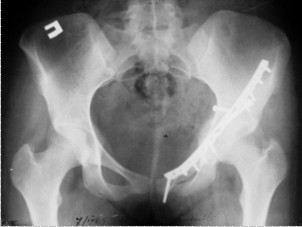

Рис. 2. Рентгенография после вправления вывиха

На 17-й день после стабилизации общего состояния и соответствующей предоперационной подготовки, передним илиоингвинальным доступом была произведена операция. Примущество этого доступа в том, что он позволяет, главным образом, подойти к передней колонне, а также дает возможность подойти к задней колонне при помощи манипуляций квадратной поверхностью. Репозиция суставной поверхности не может быть непосредственно визуализирована, однако, восстановление контуров верхней апертуры таза позволяет предположить ее реализацию. Во время операции в качестве репонаторов были использованы специальные остроконечные тазовые костодержатели, а в качестве фиксаторов–винты и реконструкционная пластина. Ниже представлены послеоперационные рентгенограммы (рис. 3, 4).

Рис. 3. Прямая проекция

Рис. 4. Подвздошная проекция